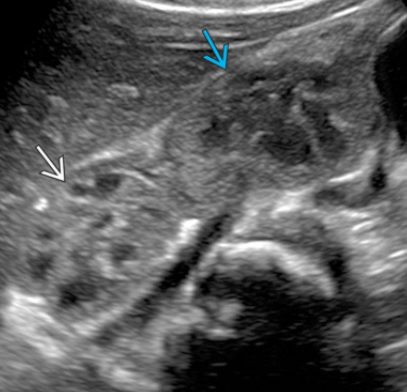

Reins

- Malformations rénales

- Absence d’un rein

Crossed-fused ectopia